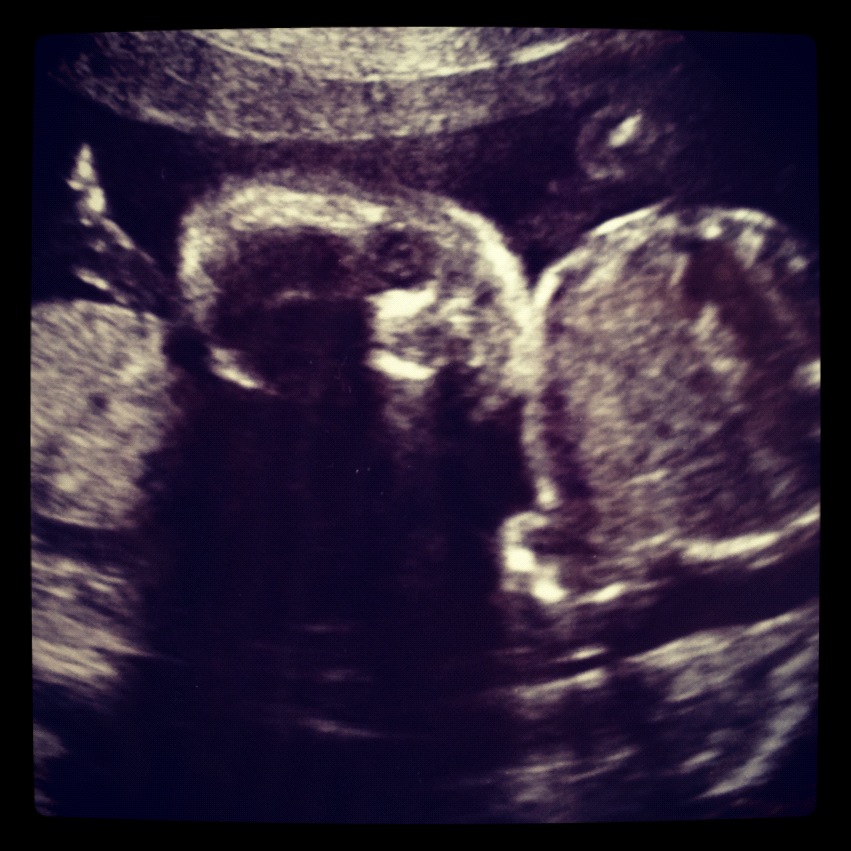

Today the baby is 20 weeks. At the doctors office, we got to see the baby again. She smiled at us! So amazing! This made my day!